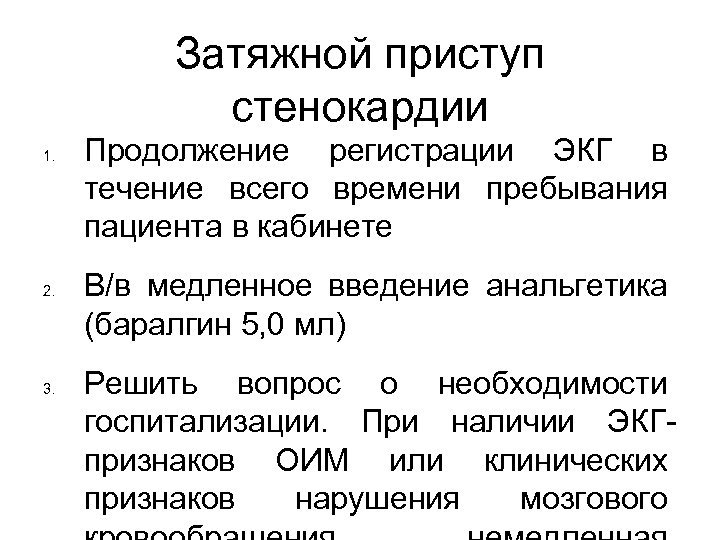

Затяжной приступ стенокардии 1. 2. 3. Продолжение регистрации ЭКГ в течение всего времени пребывания пациента в кабинете В/в медленное введение анальгетика (баралгин 5, 0 мл) Решить вопрос о необходимости госпитализации. При наличии ЭКГпризнаков ОИМ или клинических признаков нарушения мозгового

Затяжной приступ стенокардии 1. 2. 3. Продолжение регистрации ЭКГ в течение всего времени пребывания пациента в кабинете В/в медленное введение анальгетика (баралгин 5, 0 мл) Решить вопрос о необходимости госпитализации. При наличии ЭКГпризнаков ОИМ или клинических признаков нарушения мозгового